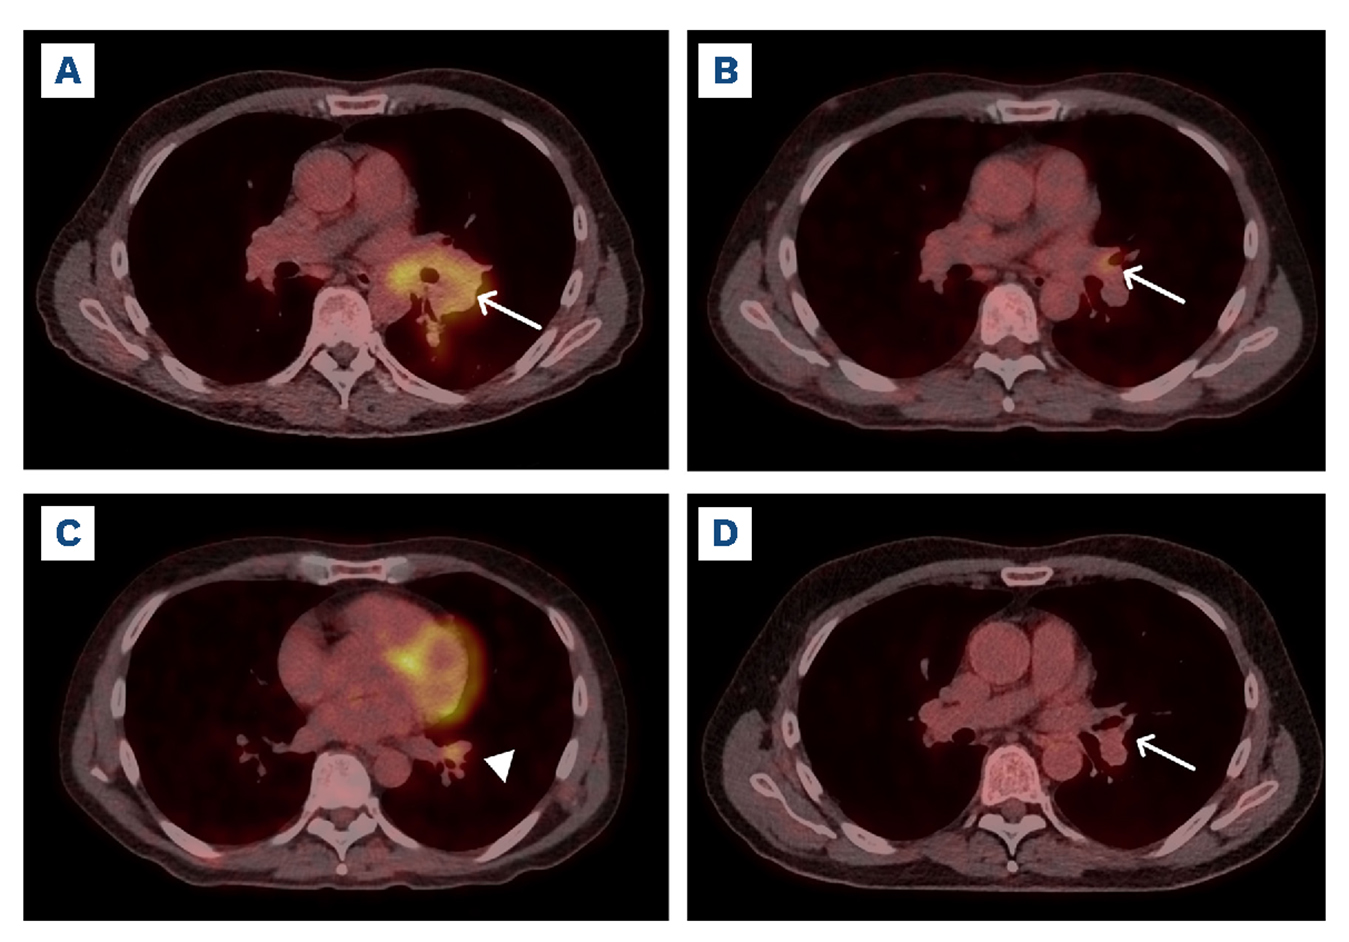

The patient was started on intravenous ceftriaxone 2 g once daily for 2 weeks, followed by oral trimethoprim/ sulfamethoxazole (TMP/SMX) 160/800 mg twice daily for 1 year. Over the next months, the index lesion at the left hilum decreased in both size and metabolic activity on 18F-FDG PET/CT, as shown in Figure 1B. A new lesion appeared at the left lower hilum, as depicted in Figure 1C, which was primarily suspicious for lymph node progression due to its location and FDG-avidity. However, the patient refused biopsy of the new lesion, and based on the clinical remission of any symptoms, antibiotic therapy with TMP/SMX was continued. Serial 18F-FDG PET/CT imaging demonstrated a slow and steady decrease of both lesions, which finally disappeared after 1 year of antibiotic therapy. Complete remission was still maintained at the last follow-up 27 months after initiation of treatment, as shown in Figure 1D.

Figure 1.F18-FDG positron emission tomography/computed tomography staging at the time of diagnosis and restaging 4 months and 27 months after treatment initiation. (A) Staging at the time of diagnosis found a pathologic fluorodeoxyglucose (FDG) uptake in a left hilar mass (white arrow) with a maximum diameter of 6.0 cm and a maximum standardized uptake value (SUVmax) of 13.0. (B) Restaging after 4 months of antibiotic treatment showed a decrease in size and FDG uptake of the index lesion (white arrow), with a SUVmax of 4.8. (C) Restaging after 4 months also indicated a new 3.0 cm lesion at the left lower hilum (arrowhead), with a SUVmax of 5.1. (D) At the last follow-up 27 months after treatment initiation, positron emission tomography/computed tomography showed complete metabolic and morphologic resolution of both lesions at the left hilum, as indicated by the white arrow, that marks the position of the former index lesion.